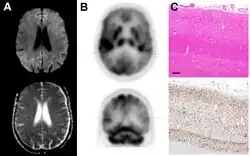

Histopathology

Spongiform change in CJD

Testing of tissue remains the most definitive way of confirming the diagnosis of CJD, although even a biopsy is not always conclusive.[56]

In one-third of people with sporadic CJD, deposits of "prion protein (scrapie)", PrPSc, can be found in the skeletal muscle or the spleen.[57] Diagnosis of vCJD can be supported by biopsy of the tonsils, which harbor significant amounts of PrPSc; however, biopsy of brain tissue is the definitive diagnostic test for all other forms of prion disease. Due to its invasiveness, a biopsy will not be done if clinical suspicion is sufficiently high or low. A negative biopsy does not rule out CJD, since it may predominate in a specific part of the brain.[58]

The classic histologic appearance is spongiform change in the gray matter: the presence of many round vacuoles from one to 50 micrometers in the neuropil, in all six cortical layers in the cerebral cortex, or with diffuse involvement of the cerebellar molecular layer.[59] These vacuoles appear glassy or eosinophilic and may coalesce. Neuronal loss and gliosis are also seen.[60] Plaques of amyloid-like material can be seen in the neocortex in some cases of CJD.[61]

However, extra-neuronal vacuolization can also be seen in other disease states. Diffuse cortical vacuolization occurs in Alzheimer's disease, and superficial cortical vacuolization occurs in ischemia and frontotemporal dementia. These vacuoles appear clear and punched out. Larger vacuoles encircling neurons, vessels, and glia are a possible processing artifact.[58]